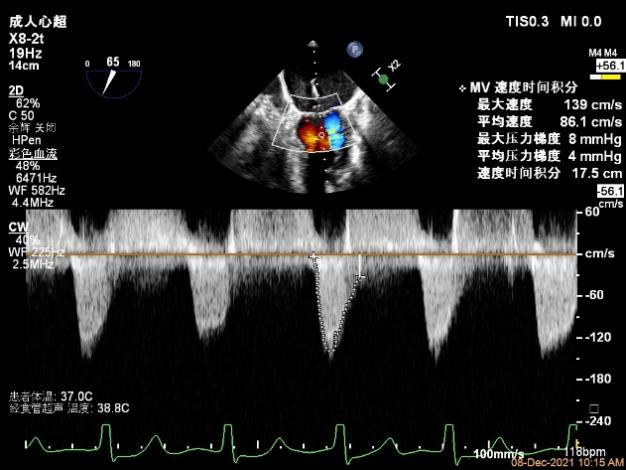

第一个夹子放置侯二尖瓣口平均跨瓣压差:4mmHg

肺静脉血流频谱恢复正向

3.、本例患者二尖瓣瓣口面积临界范围,在钳夹后我们按照规范步骤,确认二尖瓣跨瓣压差、瓣叶钳夹长度和肺静脉血流频谱改善均达到满意效果后放心释放器械,术后患者的血流动力学和临床症状迅速改善。因此,要做好不简单的病例,基石就是把每一个简单的步骤规范做好。随着我们TEER治疗经验的积累,相信不久的将来,一套标准的中国TEER临床路径将会应运而生,推动整个领域的迅速规范发展。